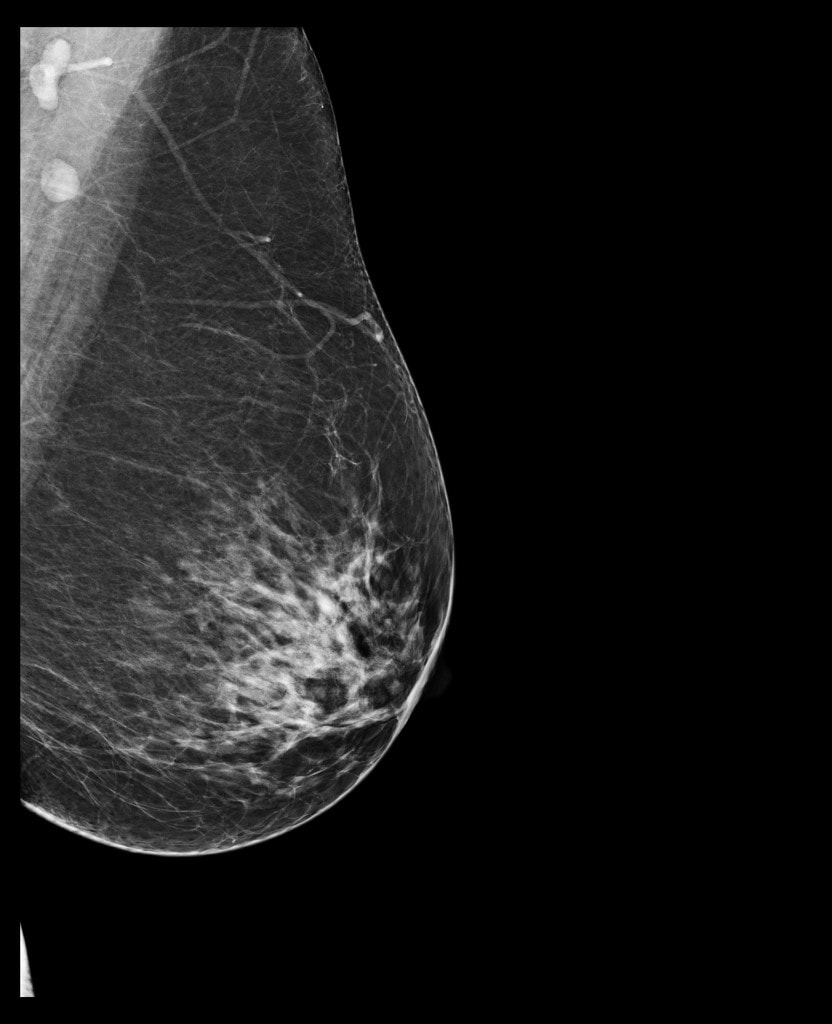

– Tessék derékig levetkőzni. Lépjen közelebb. Hajoljon kicsit le. Ne dugja a képbe a karját. Az állát fordítsa el. Most eressze le a vállát. A testével forduljon a fal felé. Dőljön előre kicsit. Fogja meg a másik kezével a rudat. Ne mozogjon. Nem jó, homályos lett, még egyszer. Ja, ezt itt el lehet forgatni. Ez egy új gép, most tanuljuk mi is. Most a másikat. Azt hittem, ez majd jobban megy. Ne rogyassza be a térdét. Húzza ki magát. Most dőljön a gép felé, és forduljon, ahogy az előbb, csak fordítva. És kicsit hajlítsa be a térdét. Öltözzön fel és üljön le kint.

– Vetkőzzön le a függöny mögött derékig. Mindent hagyjon ott. Adok lábzacskót. Adja ide a régi felvételeit. Nézzük. Ez a bal, ez a jobb. Feküdjön le. Nem, fordítva. Ez mikori? Mondtam, hogy feküdjön le. A régi CD-jét nem tudjuk beolvasni, új a gép. Ma dolgozunk vele először. Aha, ide vetíti a balt, ide a jobbat. Nem, először a bal két felvételét, aztán a jobbét együtt, összerakja. Feküdjön már le, mit nézeget. Látod, ez a kettő jön fel először. Na nézzük. Feküdjön hanyatt. Forduljon felém. Úgy, nagyon jó. Készen vagyunk. Ezt kiveszem maga alól, ezzel megtörölközhet.

kép | healthimaging.com